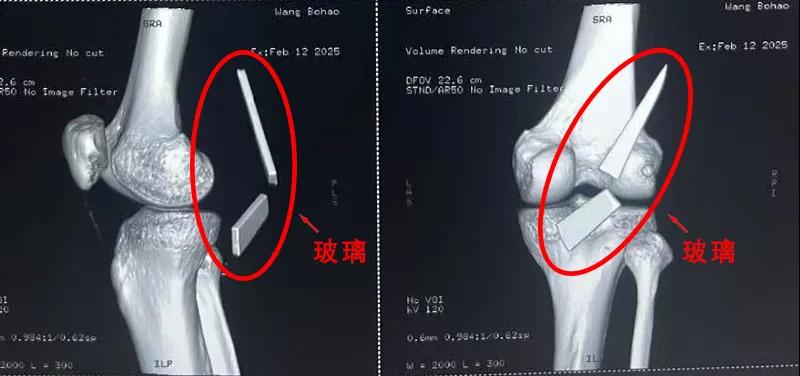

患者家屬這才開始意識(shí)到問題的嚴(yán)重性,便帶著孩子到鄉(xiāng)鎮(zhèn)衛(wèi)生院檢查——結(jié)果顯示右膝關(guān)節(jié)后方竟然殘留著兩塊兒鋒利的碎玻璃,測量后預(yù)估玻璃總長將近13厘米!

由于玻璃位置毗鄰坐骨神經(jīng)和股動(dòng)脈,一旦刺破股動(dòng)脈,將嚴(yán)重威脅生命。家屬著急萬分,想著能否盡快手術(shù)取出碎片,于是慕名來到漯河醫(yī)專二附院(漯河市骨科醫(yī)院、漯河市立醫(yī)院)手顯微外科(修復(fù)重建骨感染科)。

術(shù)中,馬廣輝醫(yī)生憑借扎實(shí)的理論知識(shí)和嫻熟的顯微外科技術(shù),順利找到深深刺進(jìn)肌肉的兩塊玻璃,肉眼可見玻璃尖端距股動(dòng)脈僅有不到半公分的距離!如果患者再耽誤半天或者再多活動(dòng)幾次膝關(guān)節(jié),小指粗的股動(dòng)脈很有可能被玻璃扎破,后果難以想象。

最終,馬廣輝醫(yī)生在血管、神經(jīng)表面順利取出兩塊玻璃碎片,拆除了埋在患者膝關(guān)節(jié)的“炸彈”。在告知患者家屬術(shù)中情況后,家屬懸著的心終于放了下來。